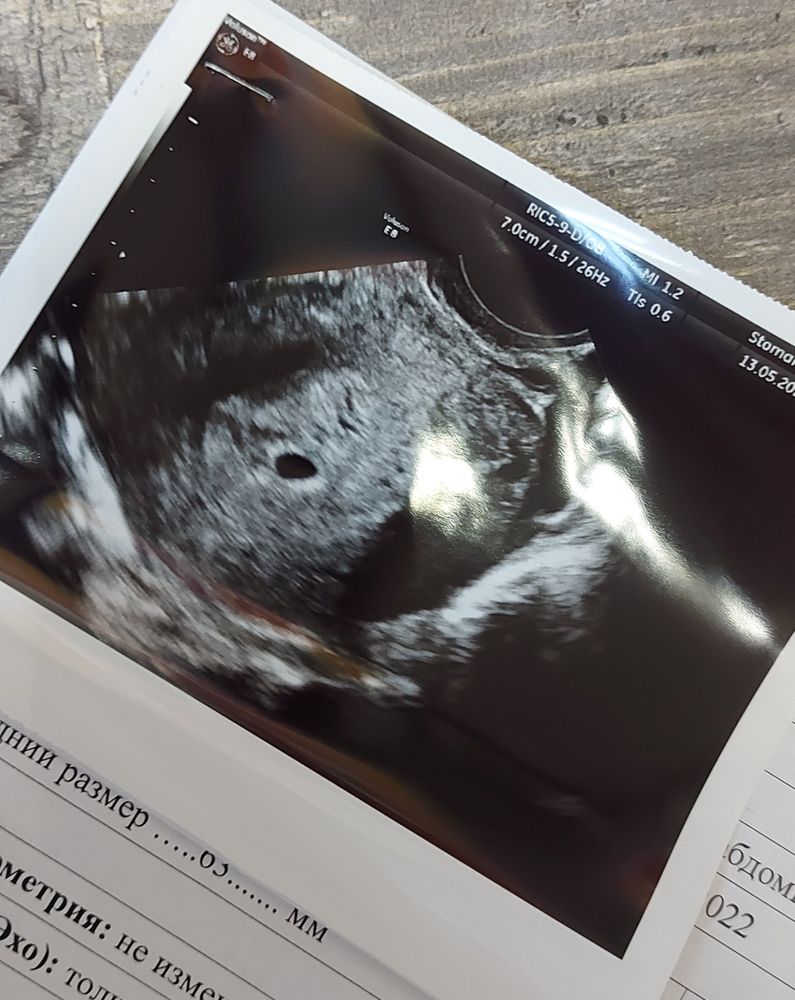

Первое УЗИ

Сегодня 10 день задержки,не собиралась так рано на УЗИ и ко врачу,но вчера начало немного мазать со сгустками и я капец как испугалась.В итоге врач сказала,что всё хорошо,нашли ПЯ 6мм,и желтое тело 15мм.Причина мазни не понятна🤔В пн пойду к своей гине,всё расспрошу. После УЗИ немного начала осознавать,что я беременна😄